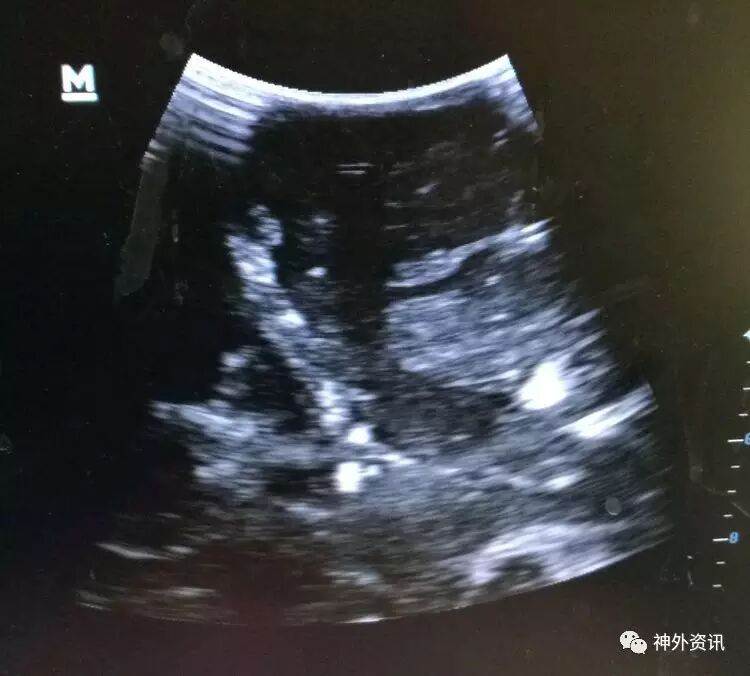

胸部CT及超声显示双肺底存在肺不张:

前胸超声:

肺底超声: